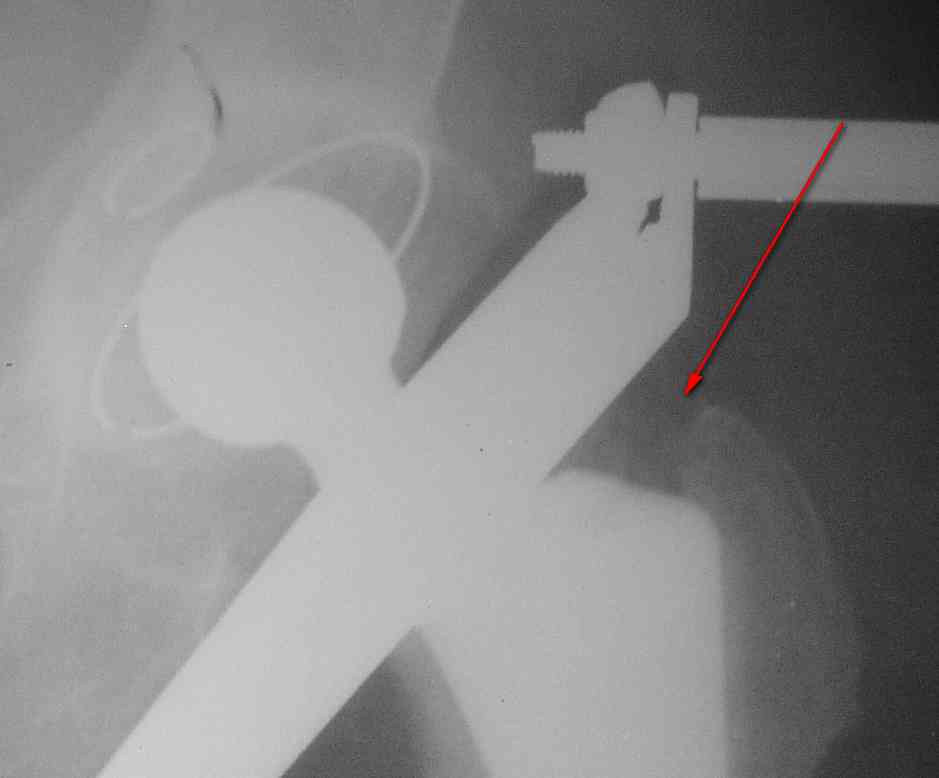

Вот фрагменты этих снимков с более различимыми областями интереса.

Видимо, тут надо добиваться точной репозиции этой спирали вдоль протеза, чтобы воссоздать ложе для ножки.